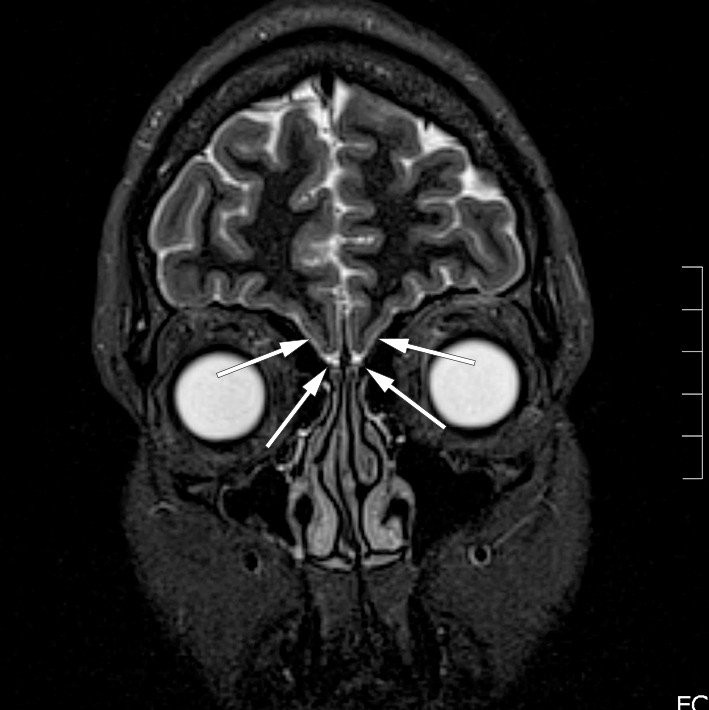

A medical history of anosmia, absence of pubertal development and low sex hormone levels prior to replacement therapy gave rise to suspicion of Kallmann syndrome, and she was referred for a new MRI of the head to determine whether the olfactory sulcus and olfactory bulb were present. The MRI revealed an absence of these bilaterally (Figure 1). Anatomical factors were therefore most consistent with Kallmann syndrome. She was referred to a geneticist and an endocrinologist, who found no other relevant pathology.

Figure 1 MRI of the head, coronal plane, 2 mm STIR sequence. The arrows show the absence of the olfactory sulcus and…

Figure 1 MRI of the head, coronal plane, 2 mm STIR sequence. The arrows show the absence of the olfactory sulcus and olfactory bulb.